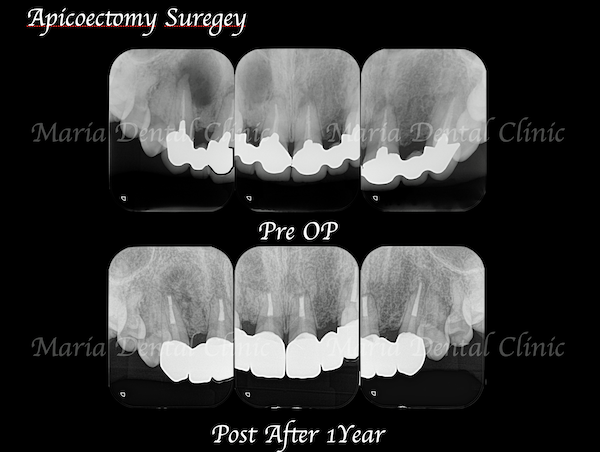

精密根管治療(歯内療法)終了後、患者様は術前同様に、特に症状は訴えていませんでした。しかし治療終了から3ヶ月経っても、病変の縮小は確認できませんでした。

患者様は今後、セラミックによる被せものを製作して、今回治療した歯に装着する予定があります。そのため、根尖性歯周炎の悪化を予防する意味も含めて歯根端切除術を行い、病変を完全に治癒させることをご提案いたしました。

精密根管治療(歯内療法)終了後1年が経過し、レントゲンでも根尖性歯周炎の治癒が確認できました。病変が大きいため、レントゲン上の治癒像は特徴的ですが、硬組織(歯や骨)の治癒は良好と判断できます。